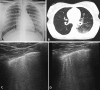

Recent evidence indicates the usefulness of lung ultrasound (LUS) in detecting coronavirus disease 19 (COVID-19) pneumonia. However, no data are available on the use of LUS in children with COVID-19 pneumonia. In this report, we describe LUS features of 10 consecutively admitted children with COVID-19 in two tertiary-level pediatric hospitals in Rome. LUS revealed signs of lung involvement during COVID-19 infection. In particular, vertical artifacts (70%), pleural irregularities (60%), areas of white lung (10%) and subpleural consolidations (10%) were the main findings in patients with COVID-19. No cases of pleural effusions were found. According to our experience, the routine use of LUS in the evaluation of children with suspected or confirmed COVID-19, when performed by clinicians with documented experience in LUS, was useful in diagnosing and monitoring pediatric COVID-19 pneumonia, reducing unnecessary radiation/sedation in children and exposure of health care workers to severe acute respiratory syndrome coronavirus 2 (SARS-CoV-2).